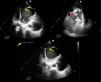

Cardiogenic shock due to a large apical pseudoaneurysm of the left ventricle: A rare complication